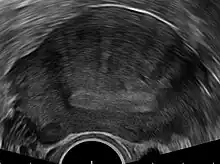

Ultrasound

Transvaginal ultrasonography is a cheap and readily available imaging test that is typically used early during the evaluation of gynecologic symptoms.[22] Ultrasound imaging, like MRI, does not use radiation and is safe for examination of the pelvis and female reproductive organs.[23] Overall, it is estimated that transvaginal ultrasonography has a sensitivity of 79% and specificity of 85% for the detection of adenomyosis.[10]

Common transvaginal ultrasound findings are defined by the European MUSA group in 2015 [24] and are defined in 2022 by the MUSA group.[25] The ultrasound characteristics can be divided in direct and indirect features.

Direct features:

- myometrial cysts - pockets of fluid within the smooth muscle of the uterus

- Hyperechogenic islands - usually white endometrium islands within the myometrium

- Echogenenic subendometrial lines and buds - usually white lines and knobs attached to the endometrium, prtruding into the myometrium.

Indirect features:

- Globular, enlarged, and/or asymmetric uterus

- Fan shaped shadowing - differentiating from fibroids with linear shadowing

- Anterior/posterior wall asymmetry

- Translational vascularity - diffuse spread of small vessels within the myometrium

- Irregular or interrupted junctional zone - the borderline between the endometrium and myometrium

The power Doppler or Doppler ultrasonography function can be used during transvaginal ultrasonography to help differentiate adenomyomas from uterine fibroids.[22][26][27] This is because uterine fibroids typically have blood vessels circling the fibroid's capsule. In contrast, adenomyomas are characterized by widespread blood vessels within the lesion.[22] Doppler ultrasonography also serves to differentiate the static fluid within myometrial cysts from flowing blood within vessels.[22]

The junction zone (JZ), or a small distinct hormone-dependent region at the endometrial-myometrial interface, may be assessed by three-dimensional transvaginal ultrasound (3D TVUS) and MRI. Features of adenomyosis are disruption, thickening, enlargement or invasion of the junctional zone.[20] There is no consensus about the actual histology of the junctional zone and a recent review showed that the ultrasound, MRI and histology all define and describe the junctional zone differently.[28]